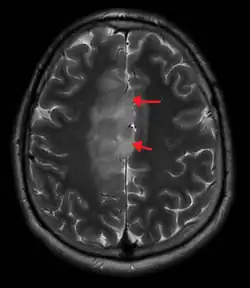

A oligoastrocytoma on MRI

An X-ray computed tomography (CT) or magnetic resonance imaging (MRI) scan is necessary to characterize the anatomy of this tumor as to size, location, and its homogeneity and heterogeneity. However, final diagnosis of this tumor, like most tumors, relies on histopathologic examination (biopsy examination).[4]